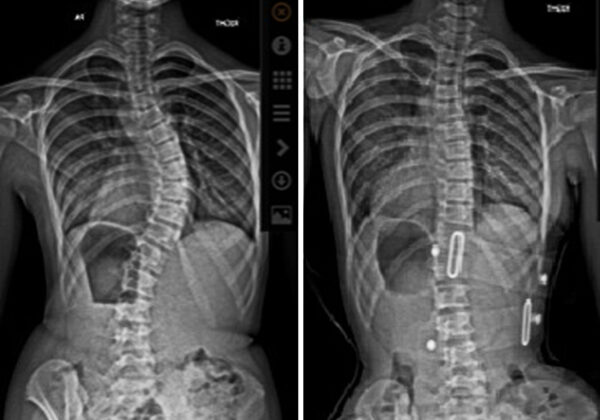

تقليديًا، كان الأطباء يقيّمون الجنف باستخدام صورة أشعة أمامية تقيس زاوية كوب فقط.

أحد أقوى المؤشرات على نجاح العلاج هو مدى تحسن زاوية كوب أثناء ارتداء الحزام مباشرة.

فكلما كانت زاوية الانحناء داخل الحزام أصغر، زادت فرصة السيطرة على الجنف على المدى الطويل.

إذا لاحظ الطبيب تحسنًا واضحًا في الأشعة داخل الحزام، فذلك مؤشر إيجابي قوي للأهل.

هل الأشعة داخل الحزام مهمة؟

نعم، فهي من أقوى المؤشرات على نجاح العلاج مستقبلًا.